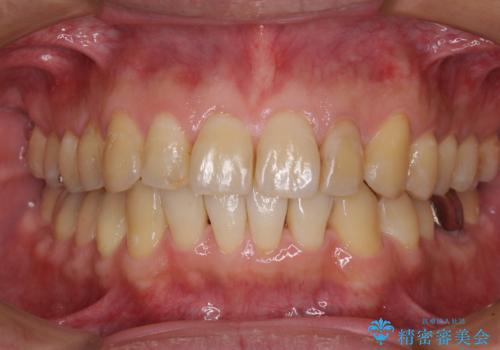

前歯のデコボコを改善 インビザライン矯正

担当医 藤巻太一朗